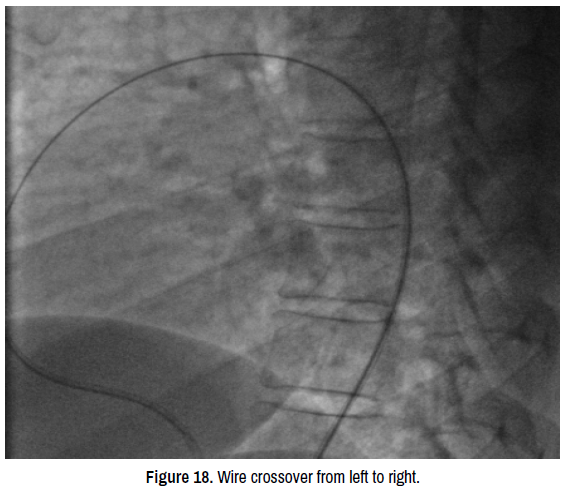

vasculitis-crossover

Figure 18. Wire crossover from left to right.

We started the procedure by sedating the child under sevoflutane with a mask and monitoring the heart rate, blood pressure and oxygen saturation. Then we proceeded to rigorous disinfection and establishment of sterile fields and punctured the right femoral artery under local anesthesia with Lidocaine 1% using 5F radial sheath. We then introduced a JR 3.5 5F diagnostic catheter on a 0.035’’ wire to the aortic isthmus and then we opaqued the channel by manual injections of ULTRAVIST 300 contrast to confirm its diameter by angiographic measurement in profile view (4.3 +/- 0.4 mm) (Figure 17). Therefore, we planned to implant a 6/8 PDA Occluder that requires a 7Fr delivery system, for that, we punctured the right femoral vein using 6fr radial sheath and injected Heparin at dose of 100 units per Kg (3000 units) then we crossed the right cavities to the pulmonary artery by a JR 3.5 5Fr diagnostic catheter on 0.035’’ wire. After failing to cross the channel by a straight hydrophilic guide 0.035’’ because of the smallness of the PDA caliber on its pulmonary side we decided to cross it by its aortic side with the hydrophilic straight 0.035’’ 260 cm wire that we exteriorized from the left JR 3.5 5Fr diagnostic catheter through the JR 3.5 5Fr diagnostic catheter mounted on the right on which we introduced the delivery system 7F by the right femoral venous access (Figure 18). The delivery system being placed from the femoral vein to the right cavities and then through the canal to the aortic isthmus, the prosthesis is debubbled and fixed by screwing on its rod then mounted in its chamber (room) under serum washing and conveyed to the end of the 7F sheath (Figure 19). We deployed the distal part of the device in the aortic isthmus and pulled back the entire system to the aortic ampulla under angiographic control (Figure 20). A traction was, then, maintained on the rod with removal of the 7Fr sheath until the device was completely deployed into the body of the channel, injections through the JR3.5 5F catheter placed in the aorta were performed close to the device confirming its correct positioning in the aortic ampulla and absence of residual shunt, comforted by an echocardiographic control (Figure 21). We proceeded to the definitive release of the device by an anti-clockwise rotation of the external part of its rod and we ended up with an echocardiographic and angiographic control with contast injection (Figure 22). A final angiographic and ultrasound control was carried out 10 minutes later in Cath Lab before the removal of the material and manual compression of the right femoral artery and vein. The procedure skin to skin took 40 minutes. A compressive bandage was placed for 12 hours. The child was monitored in the awakening room for 2 hours at the end of which she returned to the normal hospital bed.